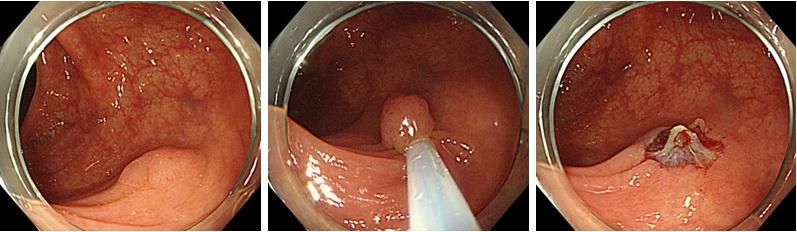

④小腸腫瘍、小腸出血

小腸カプセル内視鏡検査

長さ26mmのカプセルを水と一緒に飲み込んで頂き、あとはカプセルが自動的に写真を撮り続け、体外に装着した機械に画像データを送信します。カプセル自体は後日便と一緒に排泄されます。胃カメラ、大腸カメラを行っても出血源不明の消化管出血を主な対象としており、当院でも積極的に検査に取り組んでおります。

潰瘍形成した小腸粘膜下腫瘍

小腸内視鏡検査

当院では主にカプセル内視鏡で発見された出血源や腫瘍に対しての止血処置・精査として行っております。小腸内視鏡を常備している施設は決して多いとは言えず、近隣施設からも小腸の精査目的に多数のご紹介を頂いております。

小腸内視鏡によるクリッピング止血処置